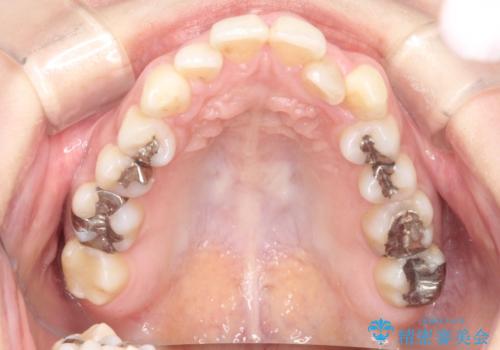

【ワイヤー矯正】前歯の凸凹を非抜歯で治療

- 前歯の凸凹を主訴に来院されました。

側方拡大にてスペースを作ることにより綺麗に前歯を並べることができました。

前歯の凸凹がある場合は治療計画を立てる上でスペースをどのように作るかが重要になります。

今回の場合は主に側方拡大でスペースの確保を行いました。